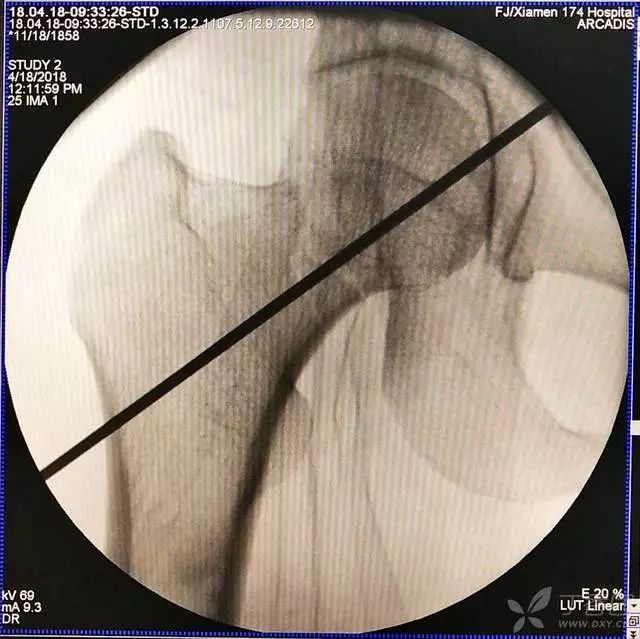

1. 对于难复性股骨颈骨折,术前应做好切开复位的准备,该患者复位三次都不太满意。

2. 倒数第二次的复位仍是欠缺一点